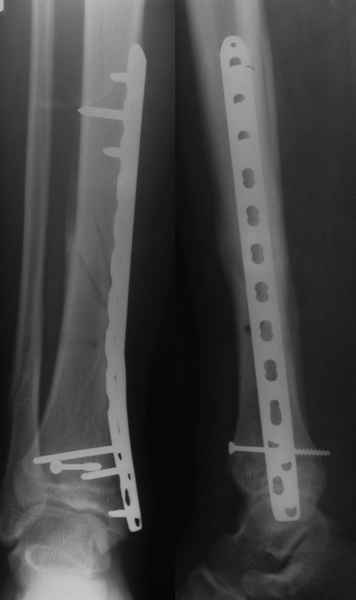

Если есть ЭОП, то перелом подходит для малоинвазивной фиксации. Репозиция суставного отдела (использовать репозиционные щипцы)и его фиксация стягивающими винтами чрезкожно, затем пластина медиально малоинвазивно, лучше метафизарная. Если не располагаете подходящим имплантом или непозволяют мягкие ткани, вполне возможно применить вместо платы Fix.Ex.

В приложении метафизарный перелом у ребёнка 14лет, с распространением линии перелома на зону роста.